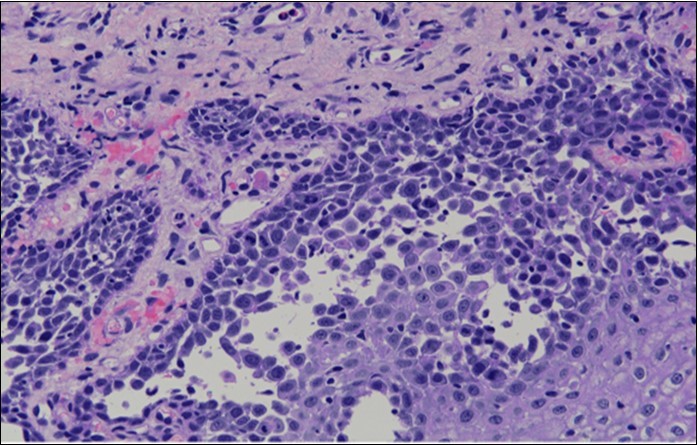

HPV test was negative for high risk subtypes of HPV. The punch biopsy specimen comprised a piece of inflamed cervical tissue in which the transformation zone was represented. The cervical tissue was covered by metaplastic and hyperplastic squamous epithelium showing intraepidermal suprabasal blister formation with acantholysis. Well vascularised dermal papillae lined residual basal cells giving rise to a tombstone appearance were present. There was no evidence of HPV, CIN, CGIN or invasive malignancy.

She was discussed at the hospital cyto-pathology conference to clarify the diagnosis. The original cytological smear specimen was reviewed, with features of bi-nucleation and koilocytosis consistent with LSIL. The cervical biopsy was also reviewed, confirming typical features suggestive of cervical pemphigus. (Figure 4a, Figure 4b, Figure 4c)

Figure 4b.Prominent acantholysis identified

Figure 4c.Well vascularised dermal papillae with residual basal layer giving rise to tombstone appearance